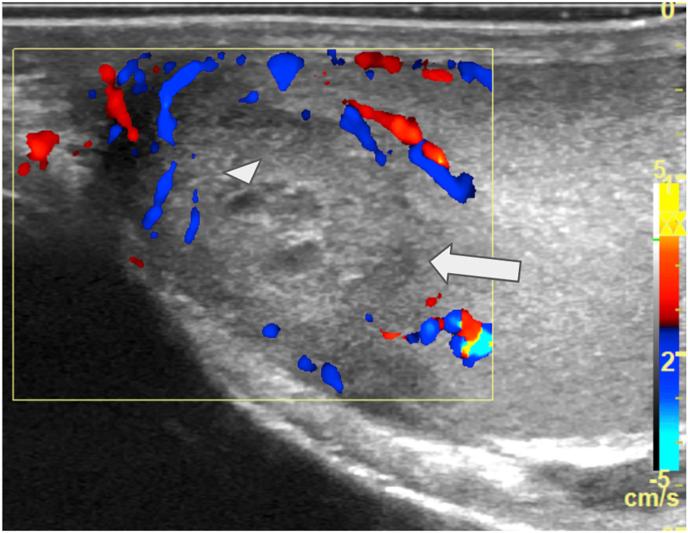

Sporotrichosis is a growing public health concern especially due . We report a case of disseminated sporotrichosis involving the meninges, lungs, and testicles in a 35-year-old homeless man from Curitiba, Brazil. Fungal culture, histopathology, and molecular identification confirmed infection. Notably, testicular involvement-a rare complication of sporotrichosis-was initially misdiagnosed as a malignant tumor, leading to orchiectomy. A literature review identified only four previous cases of testicular sporotrichosis. This case underscores the potential for atypical presentations in immunocompromised patients and highlights the need for clinical vigilance in endemic regions, given the rising incidence of sporotrichosis.